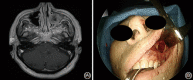

Methods: Two latex-injected cadaveric specimens were utilized to perform surgical dissections to demonstrate different approaches to the MS. The procedures were documented with macroscopic images and endoscopic pictures.

Results: Dissections were performed to approach the MS medially (endoscopic maxillary antrostomy and ethmoidectomy), anteriorly (Caldwell-Luc), superiorly (transconjunctival/transorbital approach), inferiorly (transpalatal approach), and posterolaterally (preauricular hemicoronal approach).